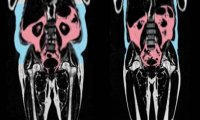

Как показало исследование стройность не гарантирует здоровье. Узнайте, как невидимый жир внутри тела старит ваше сердце и почему форма тела важнее веса.